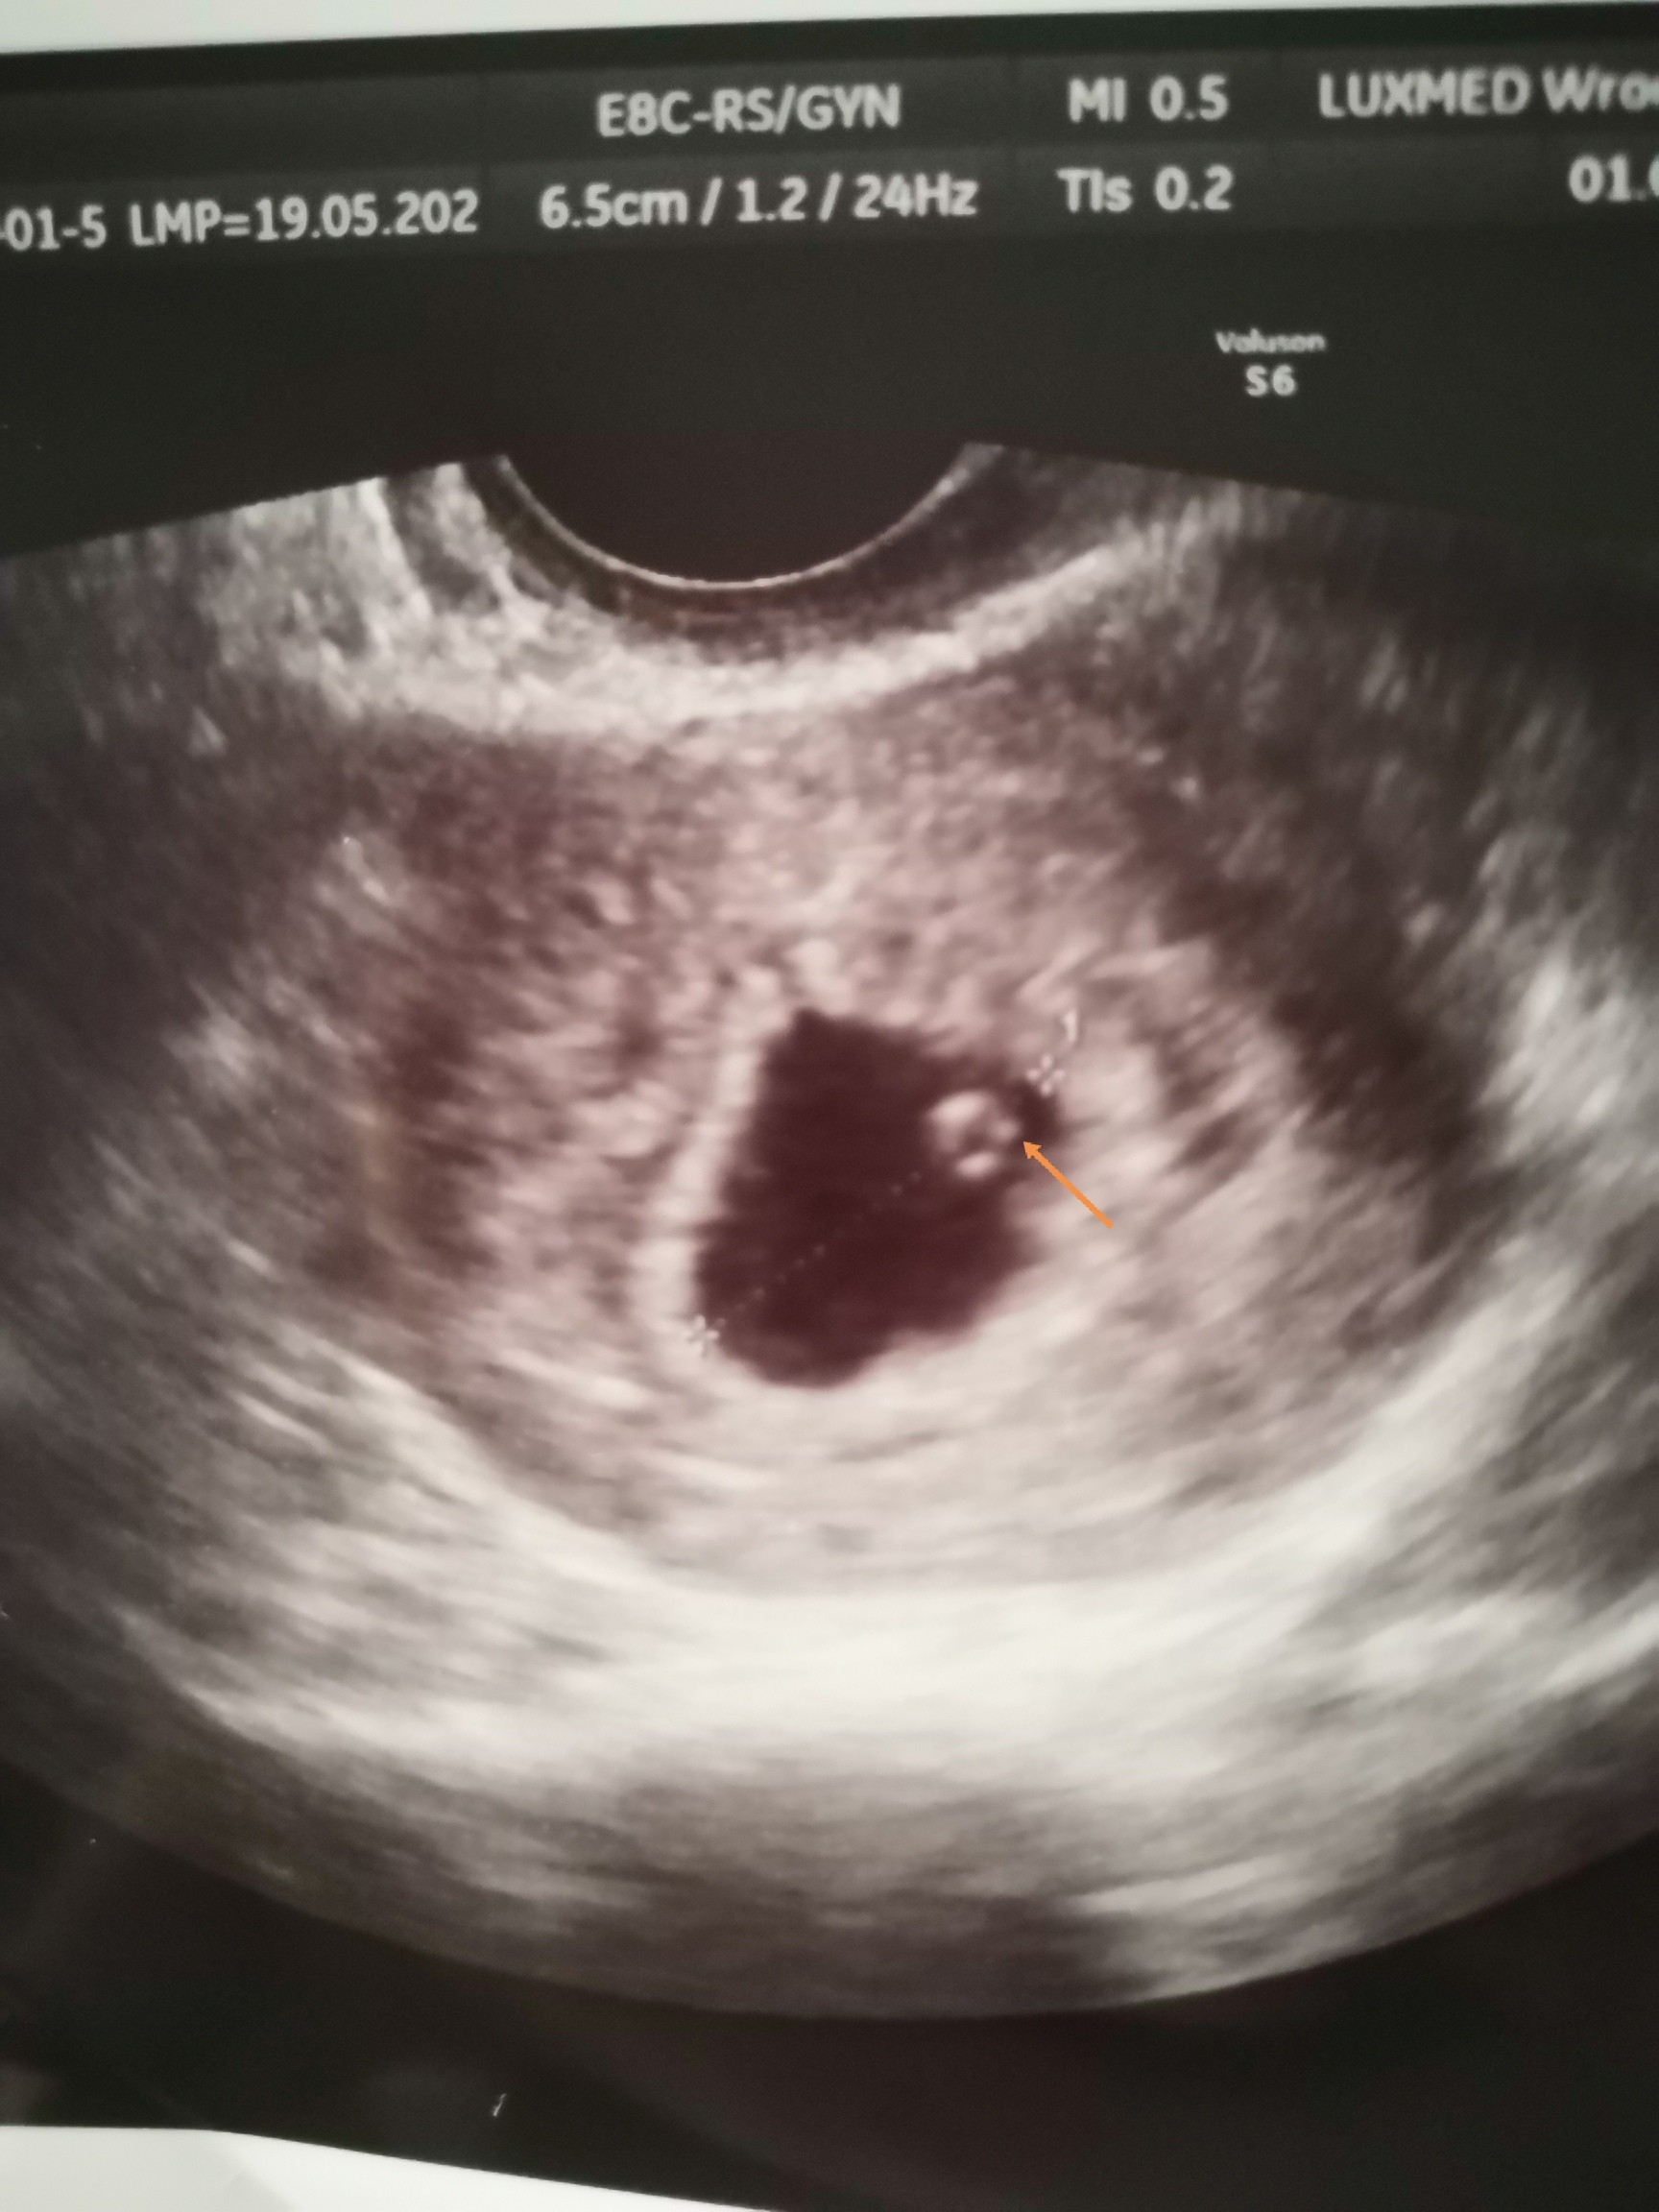

Byłam wczoraj na usg i lekarz wypatrzyl tylko pęcherzyk żółtkowy, ale mi się wydaje, że w tym miejscu co dałam strzałkę widać mikroskopijny zarodek. Co sądzicie? Pytam bo bardzo się niepokoje tym że nie widać jeszcze zarodka a jestem 6+4

• IMG_20210702_213205.jpg

IMG_20210702_213205.jpg

410,2 KB · Wyświetleń: 611